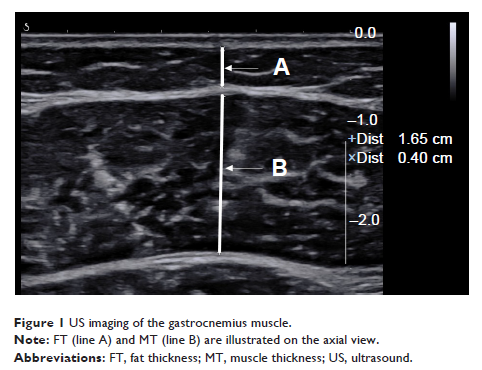

老年肌肉减少症患者腓肠肌厚度的超声测量